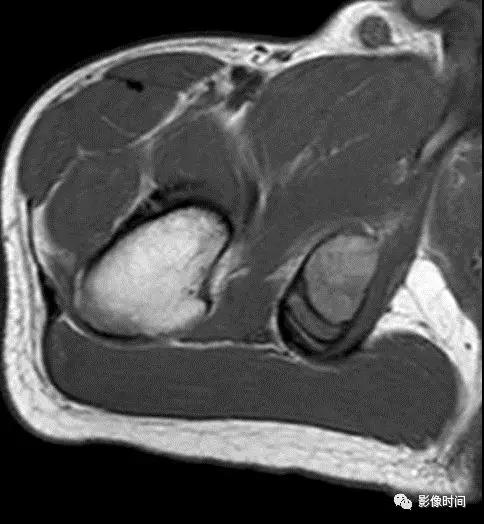

(二)瘤软骨 为肿瘤细胞产生的软骨基质,多来源于软骨类肿瘤,或内有化生瘤软骨成分的其他肿瘤如成软骨型骨肉瘤。瘤软骨为软组织密度,未钙化时,主要通过 MRI 检查显示。

由于瘤软骨多由富含水分及粘多糖的透明软骨构成,故 T1WI 呈偏低信号,T2WI 或 PDWI 呈明显高信号,被低信号的纤维间隔分开呈分叶状(图 24、图 25a-b),增强扫描多呈不均匀分隔状强化(图 25c),主要是纤维间隔强化,瘤软骨强化不明显之故。

图 24 瘤软骨:内生软骨瘤

图 25 瘤软骨:内生软骨瘤